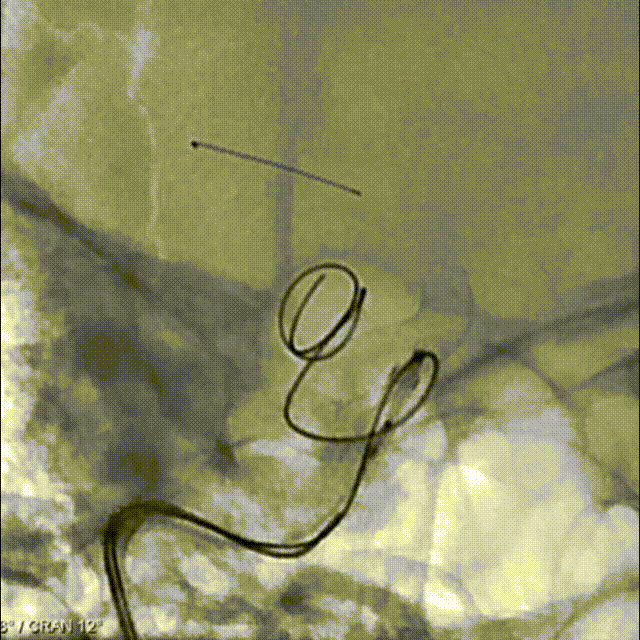

治疗过程

支架导管及弹簧圈微导管先后超选到位,其中弹簧圈微导管超选入远端眼动脉段动脉瘤内备用,根据测量结果,选用YonFlow®血流导向密网支架 4.5mm/30mm、弹簧圈9mm/40cm,先部分推出弹簧圈在动脉瘤内提供保护。再释放密网支架。

1、该病例为串联颈内动脉动脉瘤,符合密网支架应用指征。动脉瘤均位于虹吸段弯曲血管处,跨弯曲的远近段定位不理想时,需要重新回收再释放,对密网支架的操作性能(精准定位、打开贴壁等)有着较高的要求。

2、本例术中应用100%可回收的YonFlow®血流导向密网支架,支架网丝远端头端具有“球头设计”,输送顺滑,可避免管壁损伤,多次回收再释放,帮助术者实现精准定位;其钴铬合金材质网丝可以提供适宜的径向支撑力,又有较好的顺应贴壁表现;创新设计的可控解脱释放方式,可解决目前传统血流导向密网支架临床应用中面临的许多困难,在支架定位、打开贴壁、精准落点、安全性方面带来很大的提升。